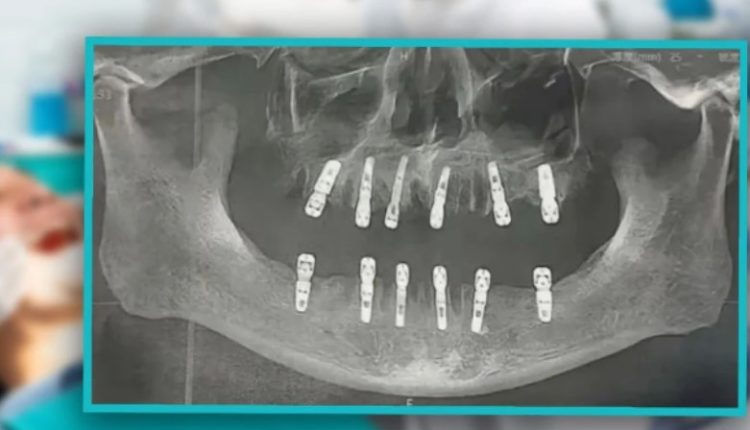

அறுவை சிகிச்சையின்போது அவரின் 23 பற்களும் பிடுங்கப்பட்டு அதே நாளில் 12 புதிய பற்கள் இம்மீடியேட் ரெஸ்டோரேஷன் (Immediate restoration) முறையில் பொருத்தப்பட்டுள்ளது.